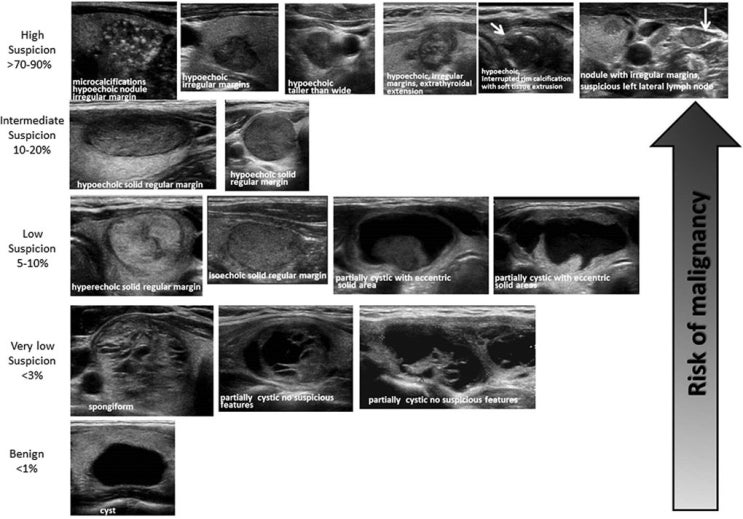

Ultrasound of thyroid nodules Thyroid Nodule Usmle It is going to go through the step by step. This video is going to discuss the evaluation of thyroid nodules. By a clinician during routine physical examination; This usmle step 2 test prep question deals with a female patient who has a solitary nodule in the thyroid gland that’s readily palpable. Workup of a thyroid nodule review for usmle. Thyroid Nodule Usmle.